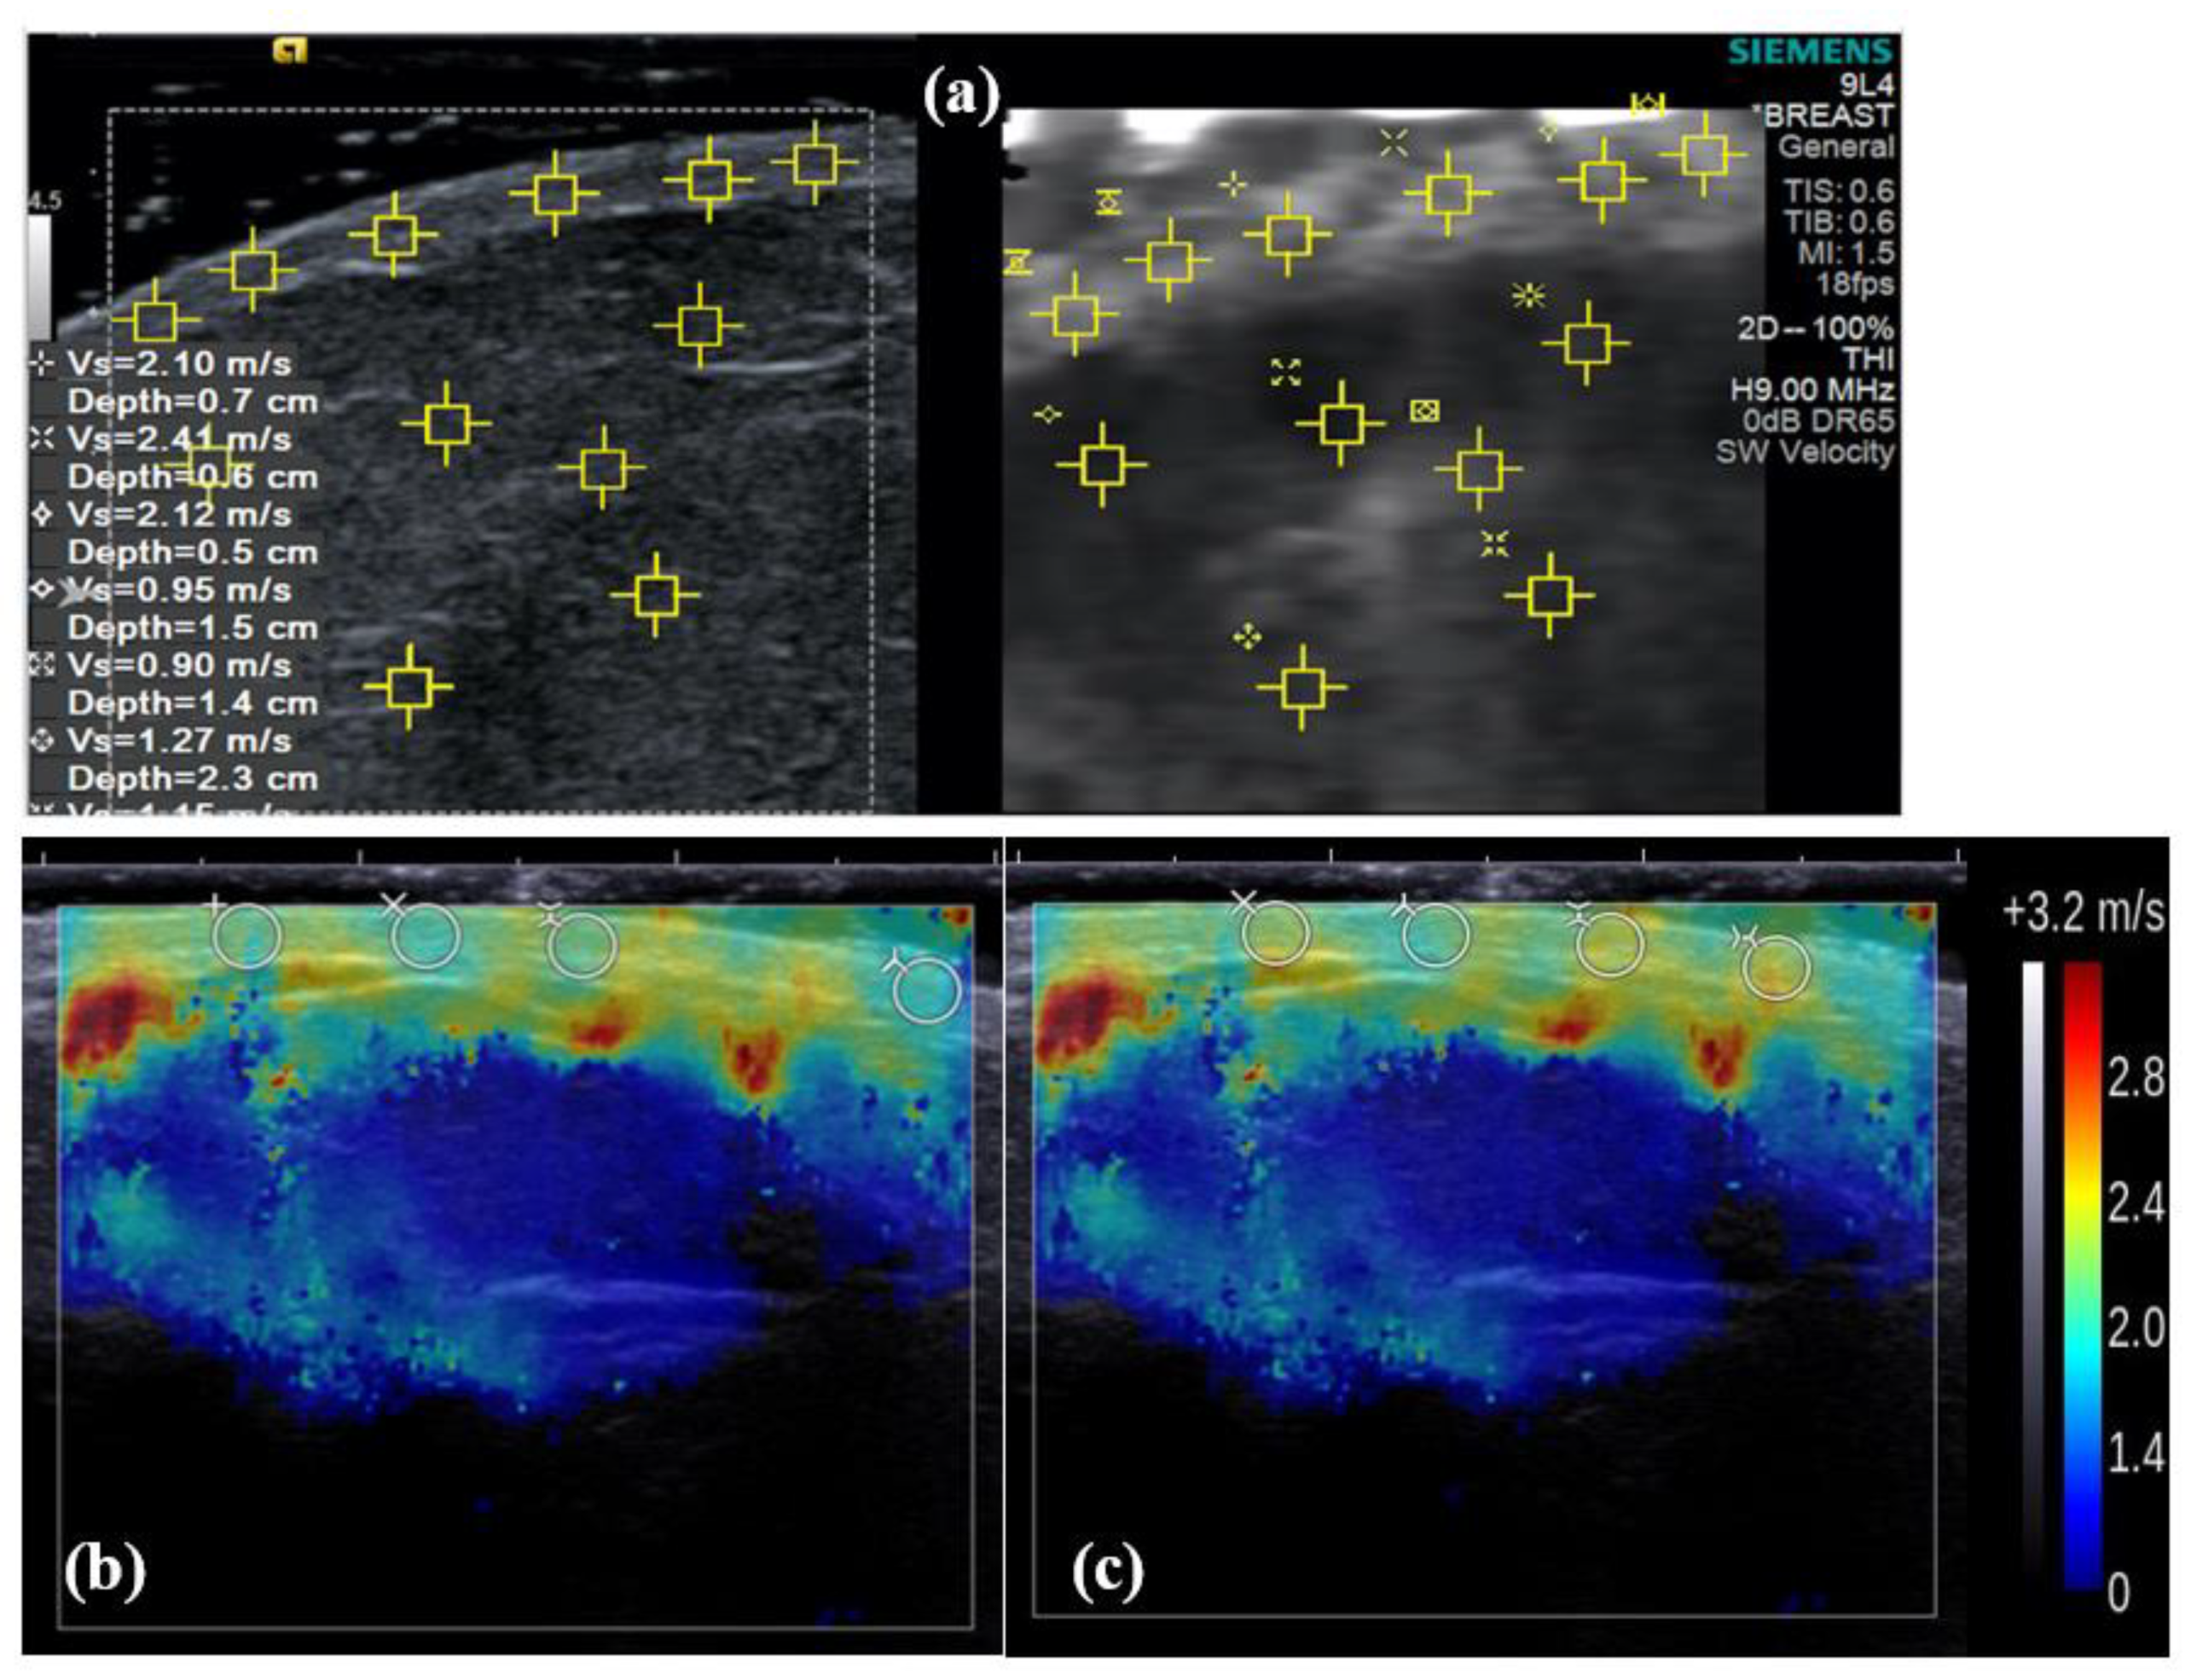

3.2. Difference in cs Estimates between Machines In Vivo

4.2. Rationale for the Exclusion of Artefacts from Aixplorer Elastogram Analysis

4.3. Difference in cs Estimates between Machines In Vivo

| Mean cs Estimate Per Elastogram (ms−1) | |||||||||

|---|---|---|---|---|---|---|---|---|---|

| Aixplorer | Aixplorer (with Artefacts) | S2000 | |||||||

| S | A | P | S | A | P | S | A | P | |

| Median | 2.4 | 2.0 | 2.2 | 3.0 | 2.9 | 3.0 | 1.6 | 1.2 | 1.3 |

| IQR | 0.9 | 0.4 | 0.6 | 0.9 | 0.4 | 0.6 | 0.3 | 0.3 | 0.3 |

| Max | 3.5 | 2.7 | 2.8 | 4.0 | 4.1 | 3.2 | 2.4 | 1.8 | 2.1 |

| Min | 1.6 | 1.5 | 1.2 | 1.8 | 1.9 | 1.2 | 1.2 | 1.0 | 1.0 |